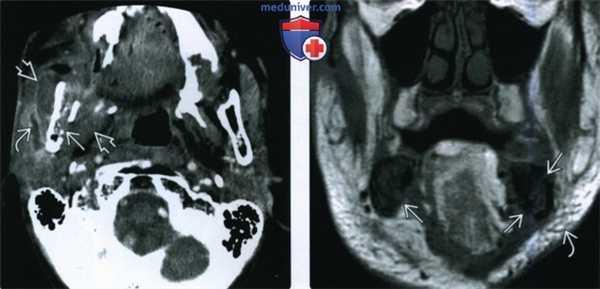

(Слева) При аксиальной КТ с КУ определяются признаки остеорадионекроза нижней челюсти справа, осложненного инфекцией жевательного пространства. Определяется дефект кортикальной пластинки, а также выраженный отек околоушной железы и жевательных мышц. Визуализируется расширенный проток околоушной железы, заполненный воспалительным дебрисом.

(Справа) При корональной МРТ Т1ВИ определяется диффузное замещение сигнала, типичного для жира, в костном мозге. Визуализируются также множеавенные дефекты кортикальной пластинки. Уплотнение и отек подкожной жировой ткани также часто обнаруживаются при ОРН нижней челюсти.

(Слева) При аксиальной КТ с КУ определяется остеорадионекроз нижней челюсти справа, осложненный инфицированием жевательного пространства. Определяется также нарушение целостности кортикальной пластинки и диффузный, выраженный отек жевательных мышц и околоушной слюнной железы, расширение ее выводного протока, заполненного дебрисом воспалительного характера.

(Справа) При МРТ Т1ВИ в корональной проекции определяется диффузное замещение сигнала, в норме наблюдающегося в костном мозге, и характерного для жира. Пристствуют множественные участки нарушения целостности кортикальной пластинки. Индурация и отек подкожных тканей являются часто встречающимися изменениями при остерадионекрозе нижней челюсти.